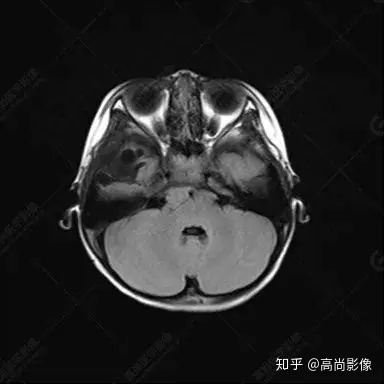

右側(cè)顳葉腫瘤切除術(shù)后(具體不詳):右側(cè)顳部骨質(zhì)不連續(xù)呈術(shù)后改變,右側(cè)顳葉術(shù)區(qū)見片狀長T1長T2信號影,F(xiàn)LAIR呈低信號;術(shù)區(qū)后方右側(cè)顳枕葉見一巨大占位性病變影,邊界欠清,大小約6.2×5.8×4.3cm(前后×左右×上下),信號不均勻,T1WI呈等稍低信號間雜少許高信號,T2WI呈高稍低混雜信號,DWI示部分病灶彌散受限,相應(yīng)ADC圖減低,磁敏感序列見部分呈極低信號,增強(qiáng)掃描可見明顯不均勻強(qiáng)化,鄰近硬腦膜及小腦幕增厚并明顯強(qiáng)化;另延髓右前方及右側(cè)橋小腦角區(qū)見一不規(guī)則形異常信號影,大小約3.2×1.3×3.7cm(左右×前后×上下),呈長T1稍長T2信號,F(xiàn)LAIR呈等信號,DWI未見受限,增強(qiáng)后明顯均勻強(qiáng)化,鄰近腦膜明顯強(qiáng)化。鄰近腦實質(zhì)及右側(cè)顳角明顯受壓;左側(cè)大腦半球未見局灶性信號異常,中線結(jié)構(gòu)稍左移。

右側(cè)顳葉腫瘤切除術(shù)后:現(xiàn)術(shù)區(qū)后方右側(cè)顳枕葉及延髓右前方占位,右側(cè)顳枕部硬腦膜及小腦幕明顯強(qiáng)化,結(jié)合既往影像資料,考慮為胚胎源性惡性腫瘤,如非典型畸胎樣/橫紋肌樣瘤(AT/RT)或原始神經(jīng)外胚層腫瘤(PNET)。

術(shù)后隨訪病理結(jié)果:非典型畸胎樣/橫紋肌樣瘤。